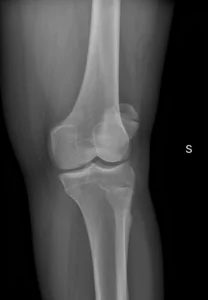

Consulta por dolor anterior de la rodilla. Sin antecedentes de trauma.

Las radiografias ap y oblicuas muestran Se identifica un fragmento óseo accesorio adyacente a la rótula, típicamente en el cuadrante superolateral, con bordes lisos y corticalizados, compatible con rótula bipartita (fallo de fusión de un centro de osificación).

El valor de este caso es evitar un error muy frecuente: confundir rótula bipartita con fractura.

Pistas a favor de rótula bipartita:

Ubicación típica superolateral (la más frecuente).

Bordes redondeados y corticalizados (no “filosos” como en fractura aguda).

Ausencia de signos claros de trauma agudo en partes blandas (según contexto).

A veces es bilateral (si tienes el otro lado, puede ayudar).

La mayoría son asintomáticas, pero puede volverse sintomática (dolor anterior) sobre todo tras actividad o trauma; en ese caso, la RM puede mostrar edema de médula ósea cerca del fragmento, lo que apoya correlación clínica.